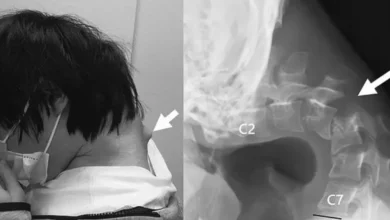

تحذير مرعب!.. هاتف ذكي يحني شاباً إلى الأبد ويشوه عموده الفقري!

تحذير مرعب!.. هاتف ذكي يحني شاباً إلى الأبد ويشوه عموده الفقري!! أطلق أطباء متخصصون تحذيراً شديد اللهجة بشأن المخاطر الصحية…